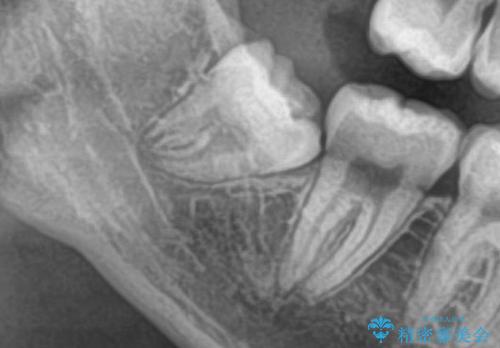

- 寝ている間に歯ぎしりをしている気がするとの事で来院。

過去にナイトガードを使用したことがあったが穴が空いてしまったそうです。

ナイトガードを使用することによって歯がすり減る(寝ている時の歯ぎしりなど)事を防いでくれます。

またナイトガードを装着して全体的に噛む力が均等になるように調整を行います。